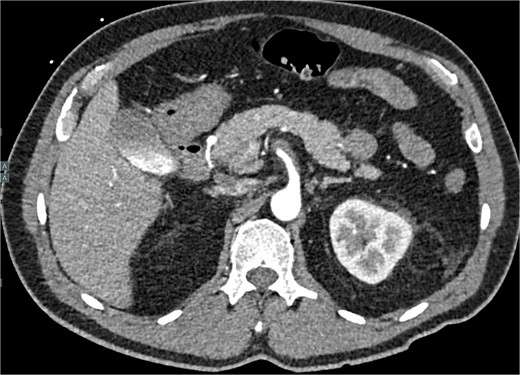

Despite medical management, the patient continued to have episodes of abdominal pain following discharge. One month after discharge, an outpatient mesenteric angiogram showed persistent SMA dissection and pseudoaneurysm. Coil embolization was performed to resolve the pseudoaneurysm. Following the procedure, the patient resumed anticoagulation therapy. The patient continued to follow outpatient studies with CTA indicating a normal SMA status post coil embolization of the pseudoaneurysm (Fig. 3).

CTA demonstrating interval embolization of SMA at site of prior thrombus and dissection.